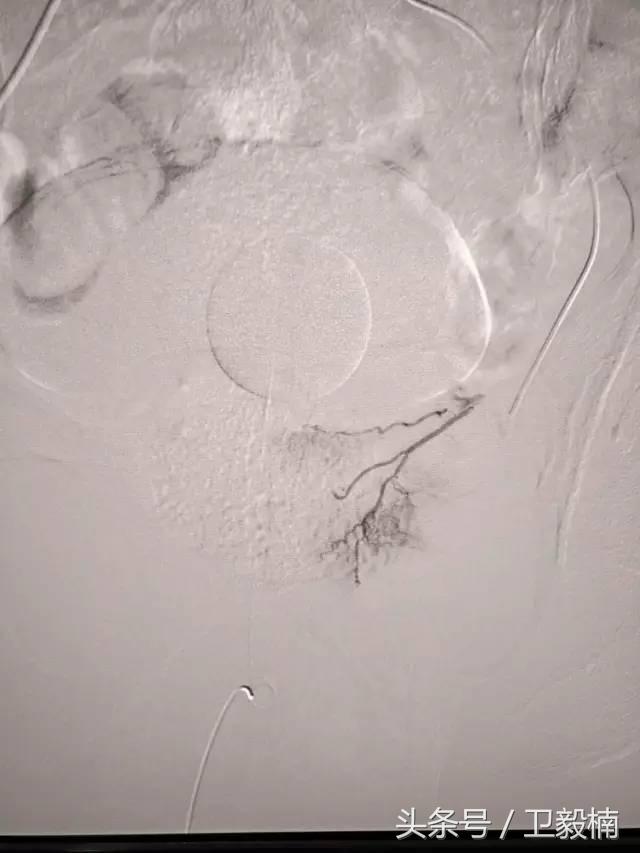

2、经导管血管栓塞法(Transcatheter embolization)

经原血管造影的导管或特制的导管,将栓塞物送至靶血管内,一是治疗内出血如外伤性脏器出血、溃疡病、肿瘤或原因未明的脏器出血。另一是用栓塞法治疗肿瘤,因肿瘤循环部分或全部被栓塞物阻断,以达控制肿瘤之生长,或作为手术切除的一种治疗手段;亦可用于非手术脏器切除,例如注射栓塞物质于脾动脉分支内,即部分性脾栓塞,以治疗脾功亢进,同时不影响脾脏的免疫功能。

常用的栓塞物质如自体血凝块、明胶海绵、无水酒精、聚乙烯醇、液体硅酮、不锈钢圈、金属或塑料小球及中药白芨等。